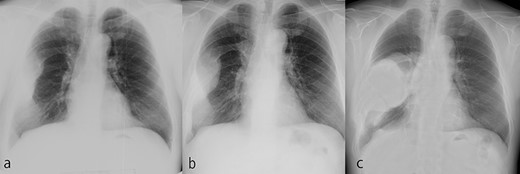

An axial CT image shows the extra-osseous tumor with calcification and cortical destruction of the right seventh rib.

A 72-year-old man was referred to our department with a suspected tumor in the right rib. An abnormal shadow in the right chest was found during screening at 50 years of age. The patient was later followed up intermittently by a general physician (Fig. 1a and b). At 72 years of age, he was referred to our department because of a suspected malignant tumor. There were neither subjective symptoms nor abnormal physical findings. A blood test revealed an elevated level for alkaline phosphatase alone at 706 U/L. A pulmonary function test showed a percent vital capacity (%VC) of 78.8%, indicating a mild restrictive impairment. Plain radiography showed a radiopaque tumor measuring 12 × 9 × 18 cm that was connected to the seventh rib in the right thoracic cavity (Fig. 1c). When compared to previous images, the tumor had gradually grown over the preceding 22 years. Computed tomography (CT) showed an extra-osseous tumor-like lesion with calcification, cortical destruction of the right seventh rib and a similar small lesion in the right ninth rib (Fig. 2). Moreover, lesions were also detected in the ninth thoracic vertebral body. Magnetic resonance imaging (MRI) revealed a lower signal intensity inside the lesion compared to the muscle on T1-weighted images and a mixture of low and high intensity on T2-weighted images, while enhancement was observed in the lower intensity area on T2-weighted images (Fig. 3a and b). Bone scintigraphy and positron emission tomography/computed tomography (PET/CT) revealed an increased uptake in the right seventh and ninth ribs and ninth vertebral body, and the right seventh rib showed a high standard uptake value at 7.67 on PET/CT (Fig. 4a and b).